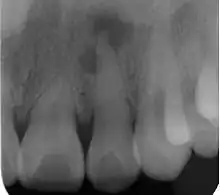

Radiograph (X-ray) showing microdontia. Note also periapical lesion on the maxillary left lateral incisor.